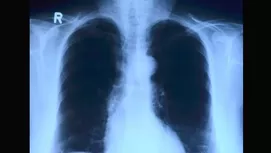

El cáncer de pulmón solo es uno de los casos más frecuentes. Está comprobado que el tabaco puede provocar cáncer de boca, labios y paladar y faringe, además de cáncer de estómago y del hígado o el cáncer de próstata.

- Fibrosis pulmonar y enfisema pulmonar, los cuales deterioran el tejido y van quitando de a poco la respiración fluida